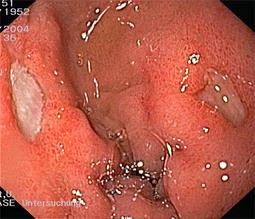

Abb. 1